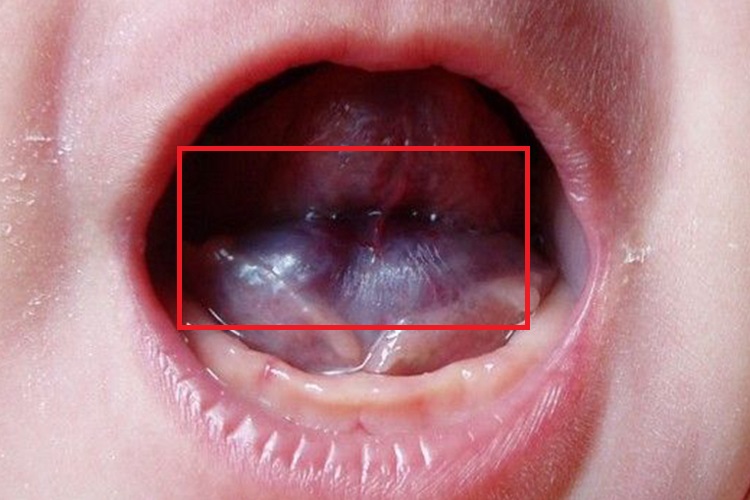

舌下血管瘤多为完全位于黏膜下的病灶,其表现为红色病灶伴深部蓝紫色包块,包块边界清楚,压之不褪色,表面多不平整,可状如草莓。可造成外观缺陷和功能障碍,病灶生长过快,可能会出现自发性溃疡。